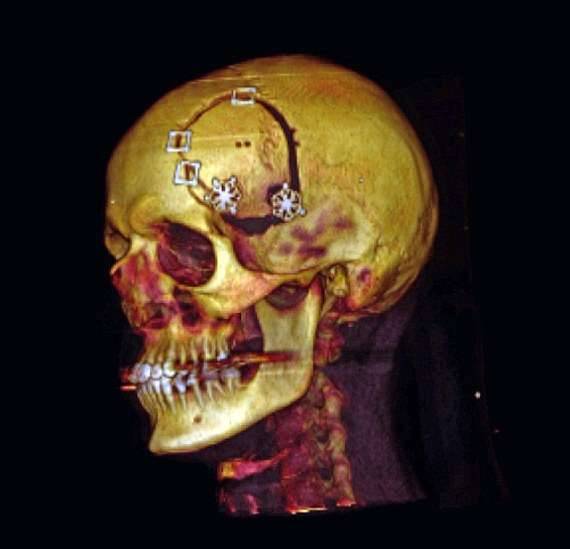

情况糟糕到不得不进行手术,在为期三个月的準备之后基廷开始了这场历时10个小时的手术,这个科学怪人要求手术过程全程录像,幸运的是手术很成功,之后的化疗用了一年的时间。

▼手术后他索取研究自己的手术录像数据甚至是自己的脑部肿瘤,他还对自己的肿瘤进行了解剖、切割、染色,获得了自己脑部研究的第一数据。